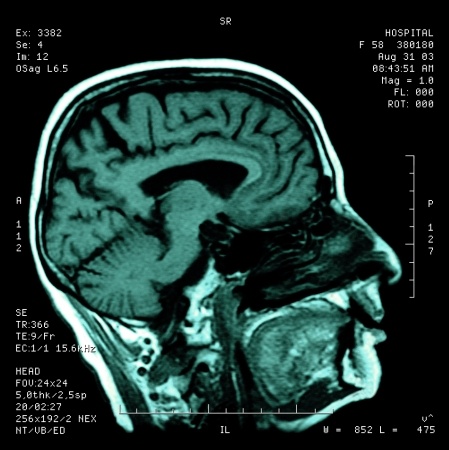

It is my experience that if you want to make long-term changes in hard to treat cases and conditions, you have to approach the problem from many different perspectives. Our approach to your health encompasses all of these components, so that we have the best chance of helping you get better. Neurologically, your brain health and it’s ability to normally receive input and stimulation from your environment (sight, sound, smell, taste, touch, hot/cold, vibration, pain, body position, etc..) has a profound influence on the health of your autonomic nervous system (sympathetic/parasympathetic) function.1 Loss of your brain’s ability to receive normal and balanced input is most commonly the result of chemical, physical or emotional stress that damages nerve pathways in the brain.1 Damage from stress to the nerve pathways in your brain is called “transneural degeneration.”1 Transneural degeneration results in a loss of normal impulse (nerve firing) between the different areas of your brain (cerebellum, thalamus, cortex, mesencephalon, ponto medullary reticular formation, intermediolateral cell column) that normally communicate and work together.1 The loss of normal brain impulse frequently causes loss of the normal regulation and balance in autonomic nervous system function.1 Loss of bilateral (because you have two halves) balance in nerve impulses between these areas of your brain can result in many of the symptoms associated with chronic pain, hormonal and autonomic nervous system dysregulation.1 I commonly find that autonomic nervous system dysregulation is a major problem in patients with chronic health problems.

In addition to addressing your health from biomechanical/orthopedic, biochemical/metabolic and functional medicine perspectives, we use functional neurology to balance nerve impulses in the weak areas of your brain. Functional neurology works because of neural plasticity, and your brain’s ability to strengthen and rewire the mesh of nerves that allow communication between the different areas in your brain. Our functional neurological and functional medicine support, in combination with biomechanical treatment of your condition is what sets us apart from other doctors.